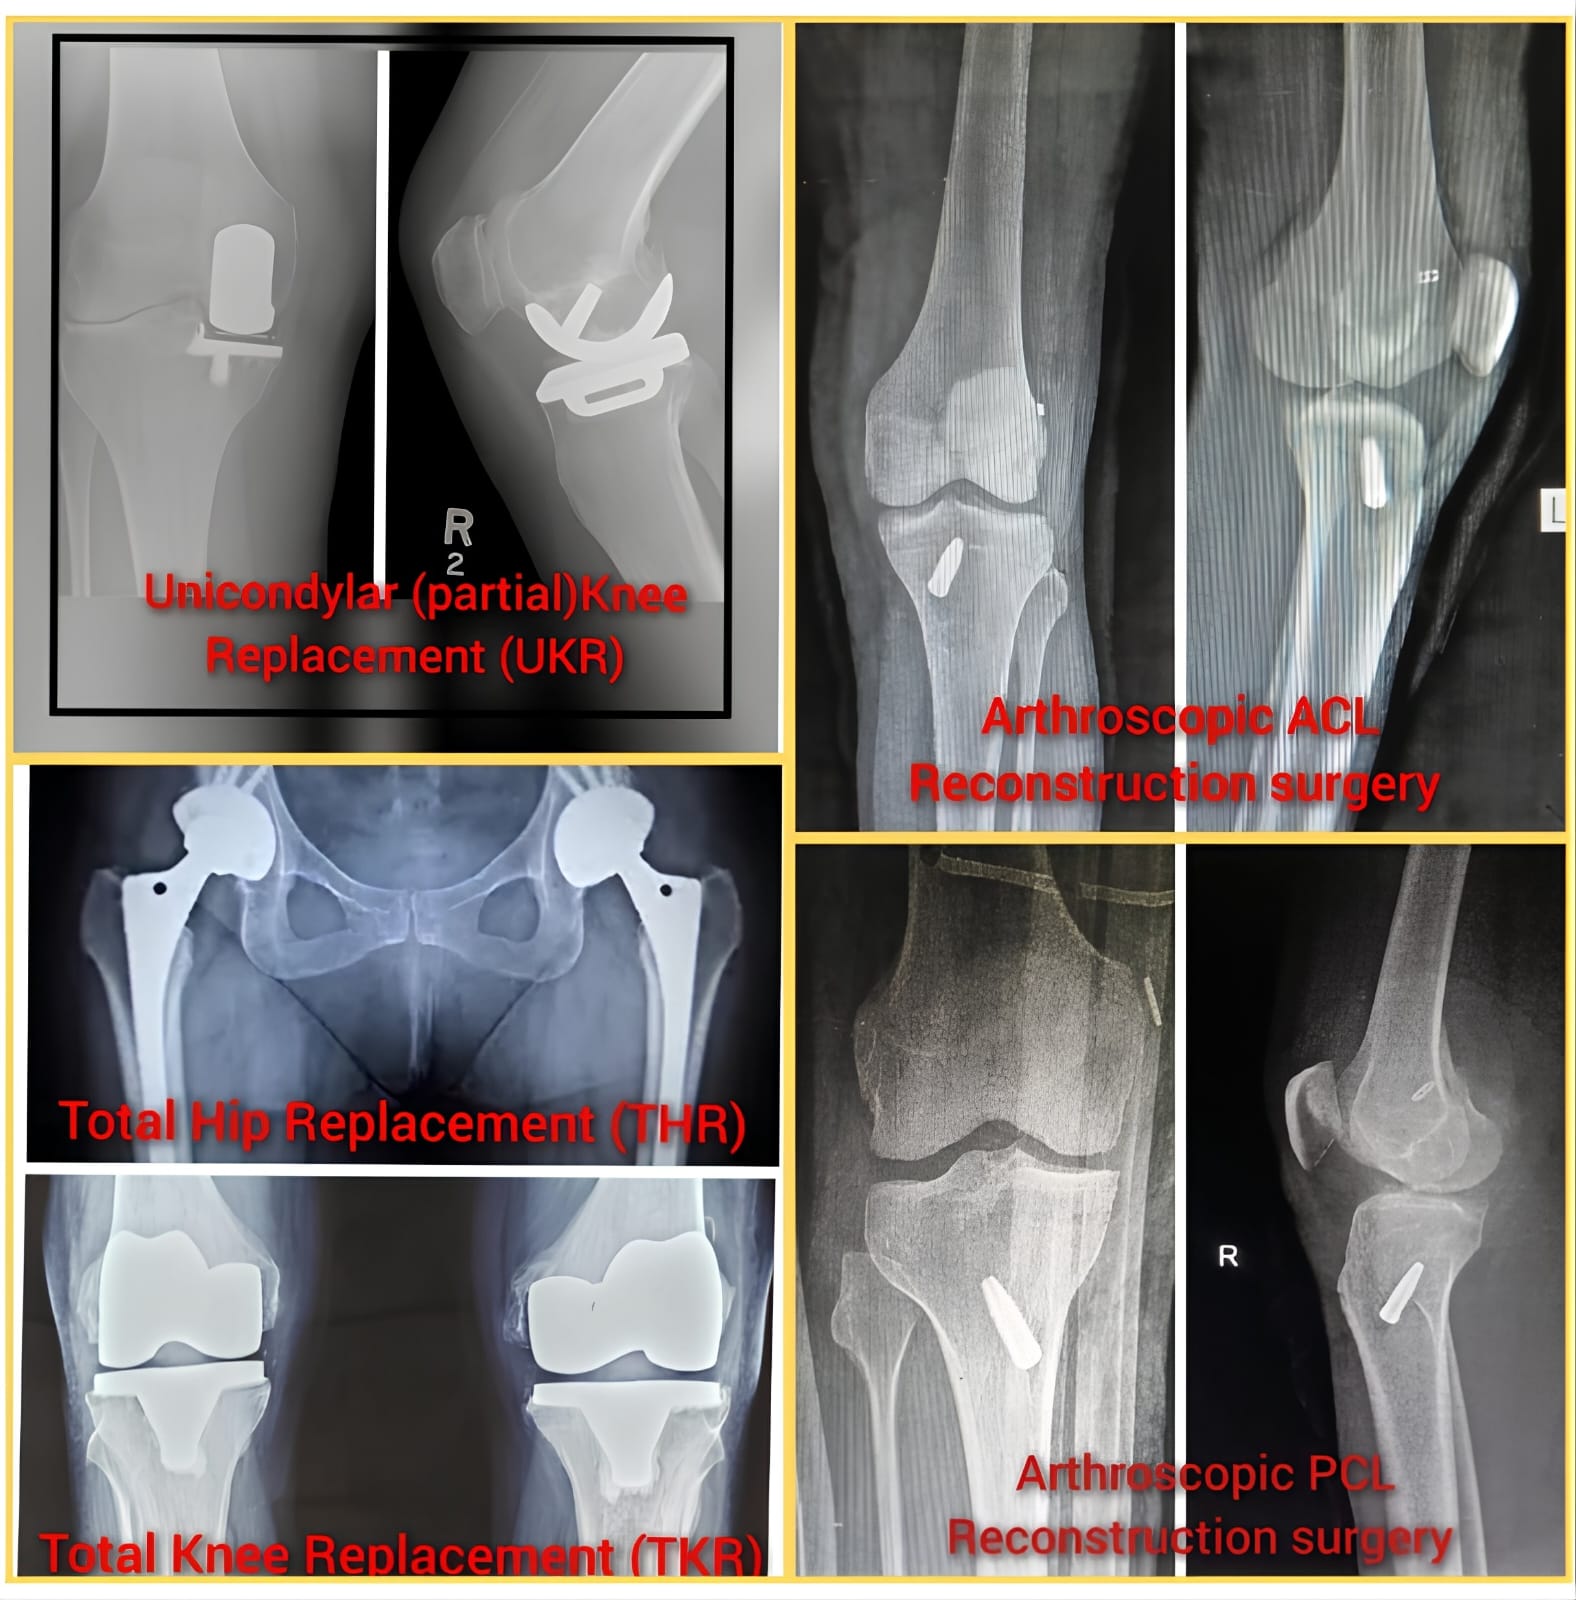

Services

Total Knee Replacement

Hip Replacement Surgery

Sports Injury Surgery

Arthroscopic Surgery

Gallery